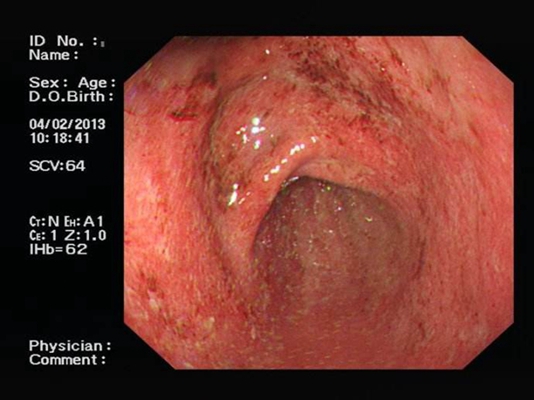

食道炎圖片